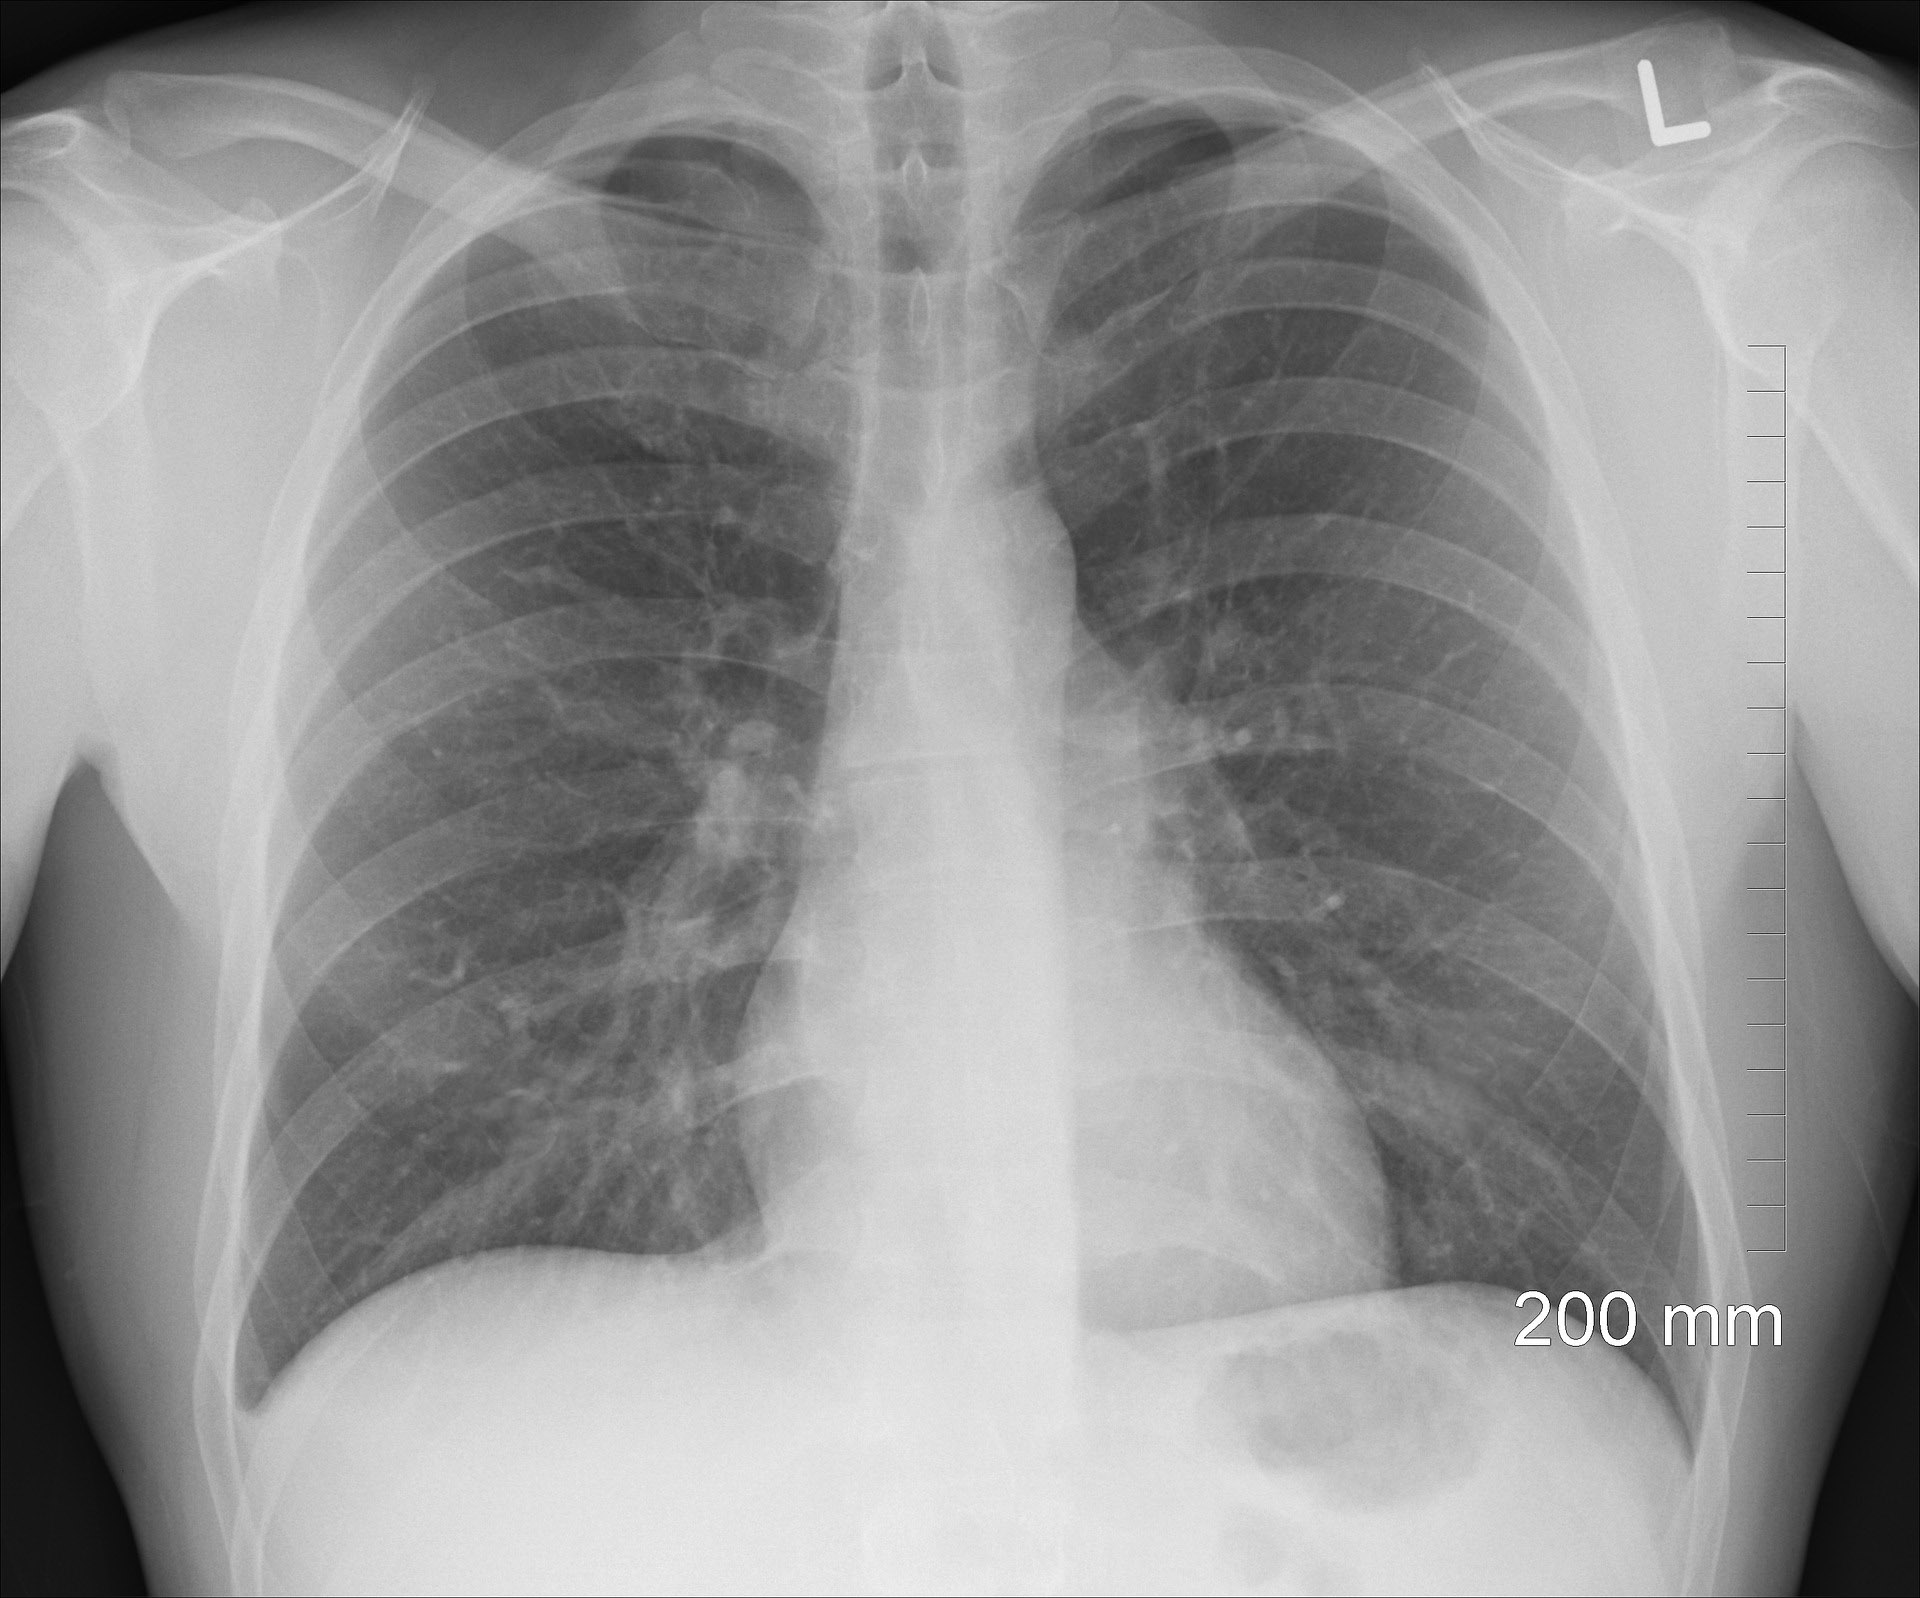

Röntgenbild Lunge